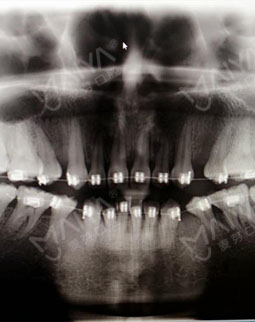

终于又等到周末啦!这一次作为患者来到麦芽,进门后客服笑盈盈的给我开门,然后填了单子,就有专人带我去见麦芽的主任了,主任和照片上一样平易近人,让我和医生的距离一下子就拉近了,耐心的听了我的苦恼。为了看一下我的牙齿,客服带着我还拍了片,这是我在之前矫正的时候没有的环节。看到电脑上显示的自己的牙齿,对这种高科技的东西着实惊了一下,相信很多人和我一样都觉得矫牙就是医生看一下,就开始戴牙套了,但是这一刻我终于明白了,矫牙并不是你以为,技术设备医生这些都很重要。

张主任指着片子说,牙齿错过了最好的矫牙年龄,而且又矫牙失败,我的属于疑难矫正了,但是还是可以矫正好的!然后为了减轻我的痛苦,让我继续戴现在的牙套,但是要分阶段调整一下,我非常开心感觉牙齿还有救,当天医生给我调整好之后,牙齿就舒服了很多,我的心情也是多云转晴!!!